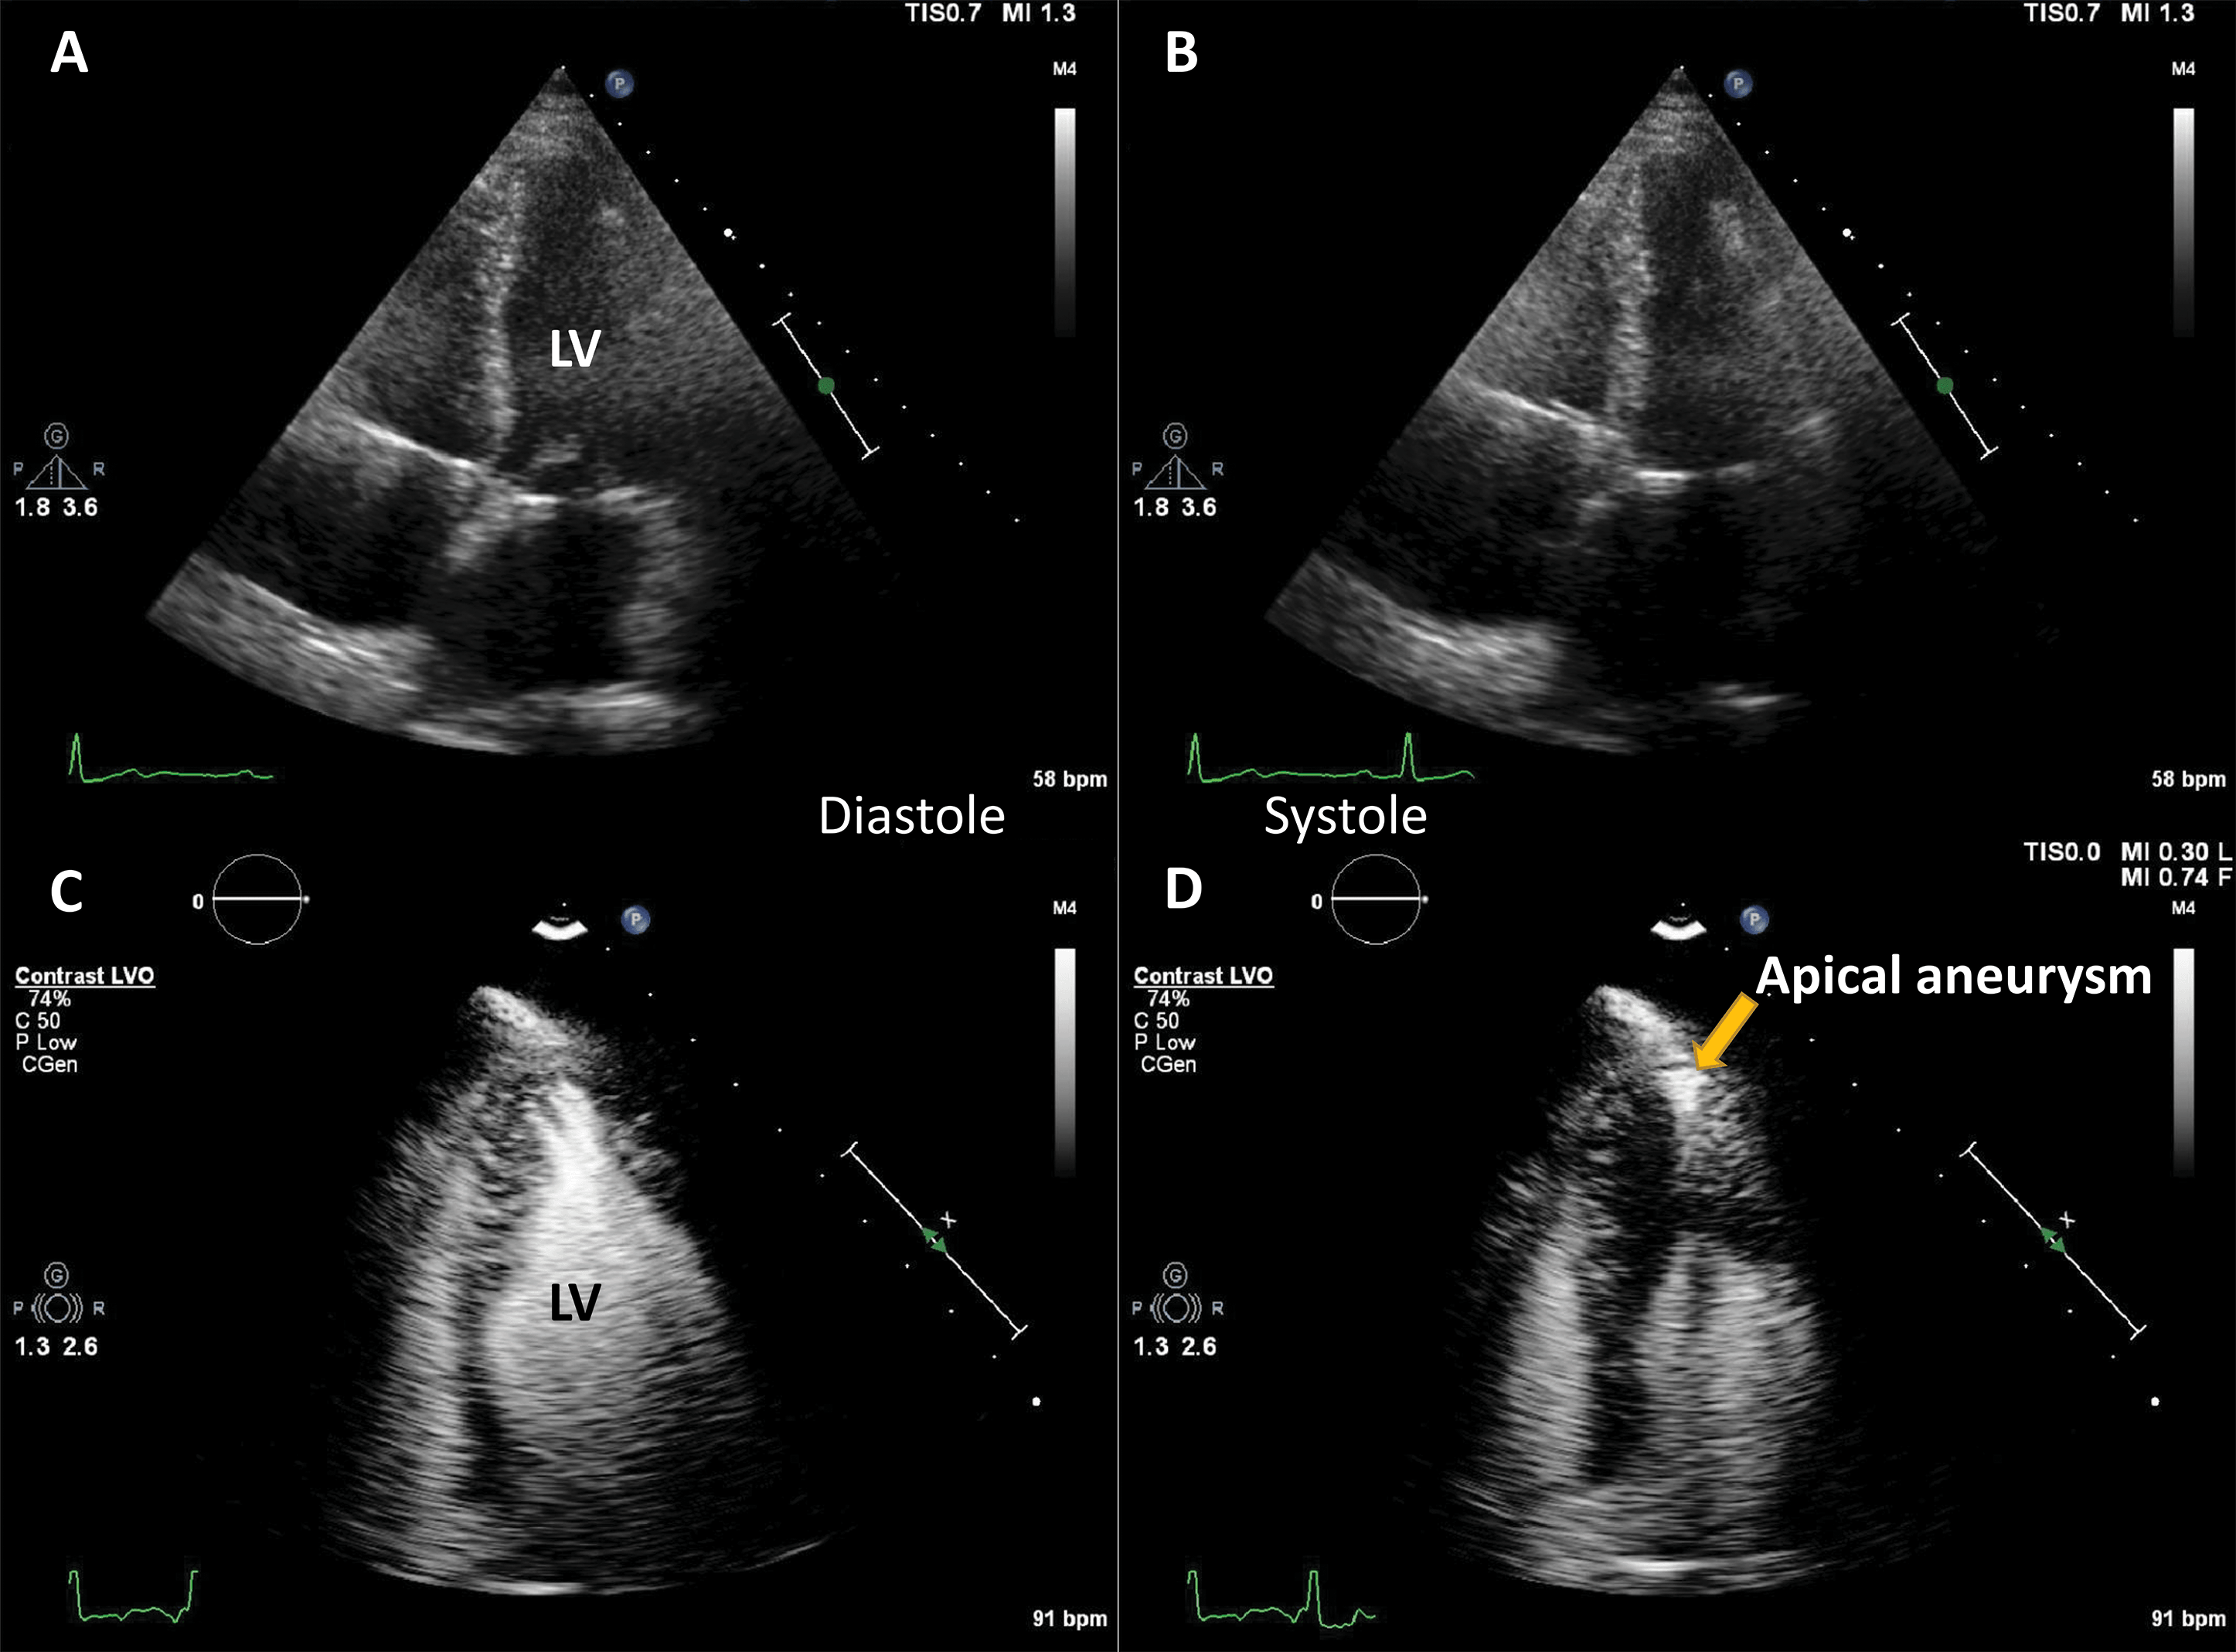

Another application of LVO is morphological diagnosis, particularly in disease states which manifest in the artefact-prone LV apex. Beside possible foreshortening, the LV apex is prone to clutter and reverberation artefacts, while also having a weaker potential to generate harmonics because of its position in the near-field in apical views [28]. As such, apical forms of hypertrophic cardiomyopathy [29, 30], eosinophilic cardiomyopathy [31] and non-compaction cardiomyopathy [32] may escape detection with unenhanced ultrasound.

Numerous case reports and case series document the use of UEA in these instances [29, 30, 31, 32, 33]. Studies have also been performed demonstrating the added value of contrast-enhanced ultrasound in hypertrophic cardiomyopathy [34] (Fig. 4, Video 4).

Fig. 4.Hypertrophic cardiomyopathy patient with very poor image in apical 4-chambers view. (A,B) Native images, end-diastole (A) and end-systole (B). The endocardium of the lateral wall is not visible, and the apex cannot be seen. (C,D) Contrast-enhanced images, in the same moments in the cardiac cycle. The LV contour is clearly delineated, during systole there is complete cavity obliteration, with an apical aneurysm (arrow). Source: personal collection.